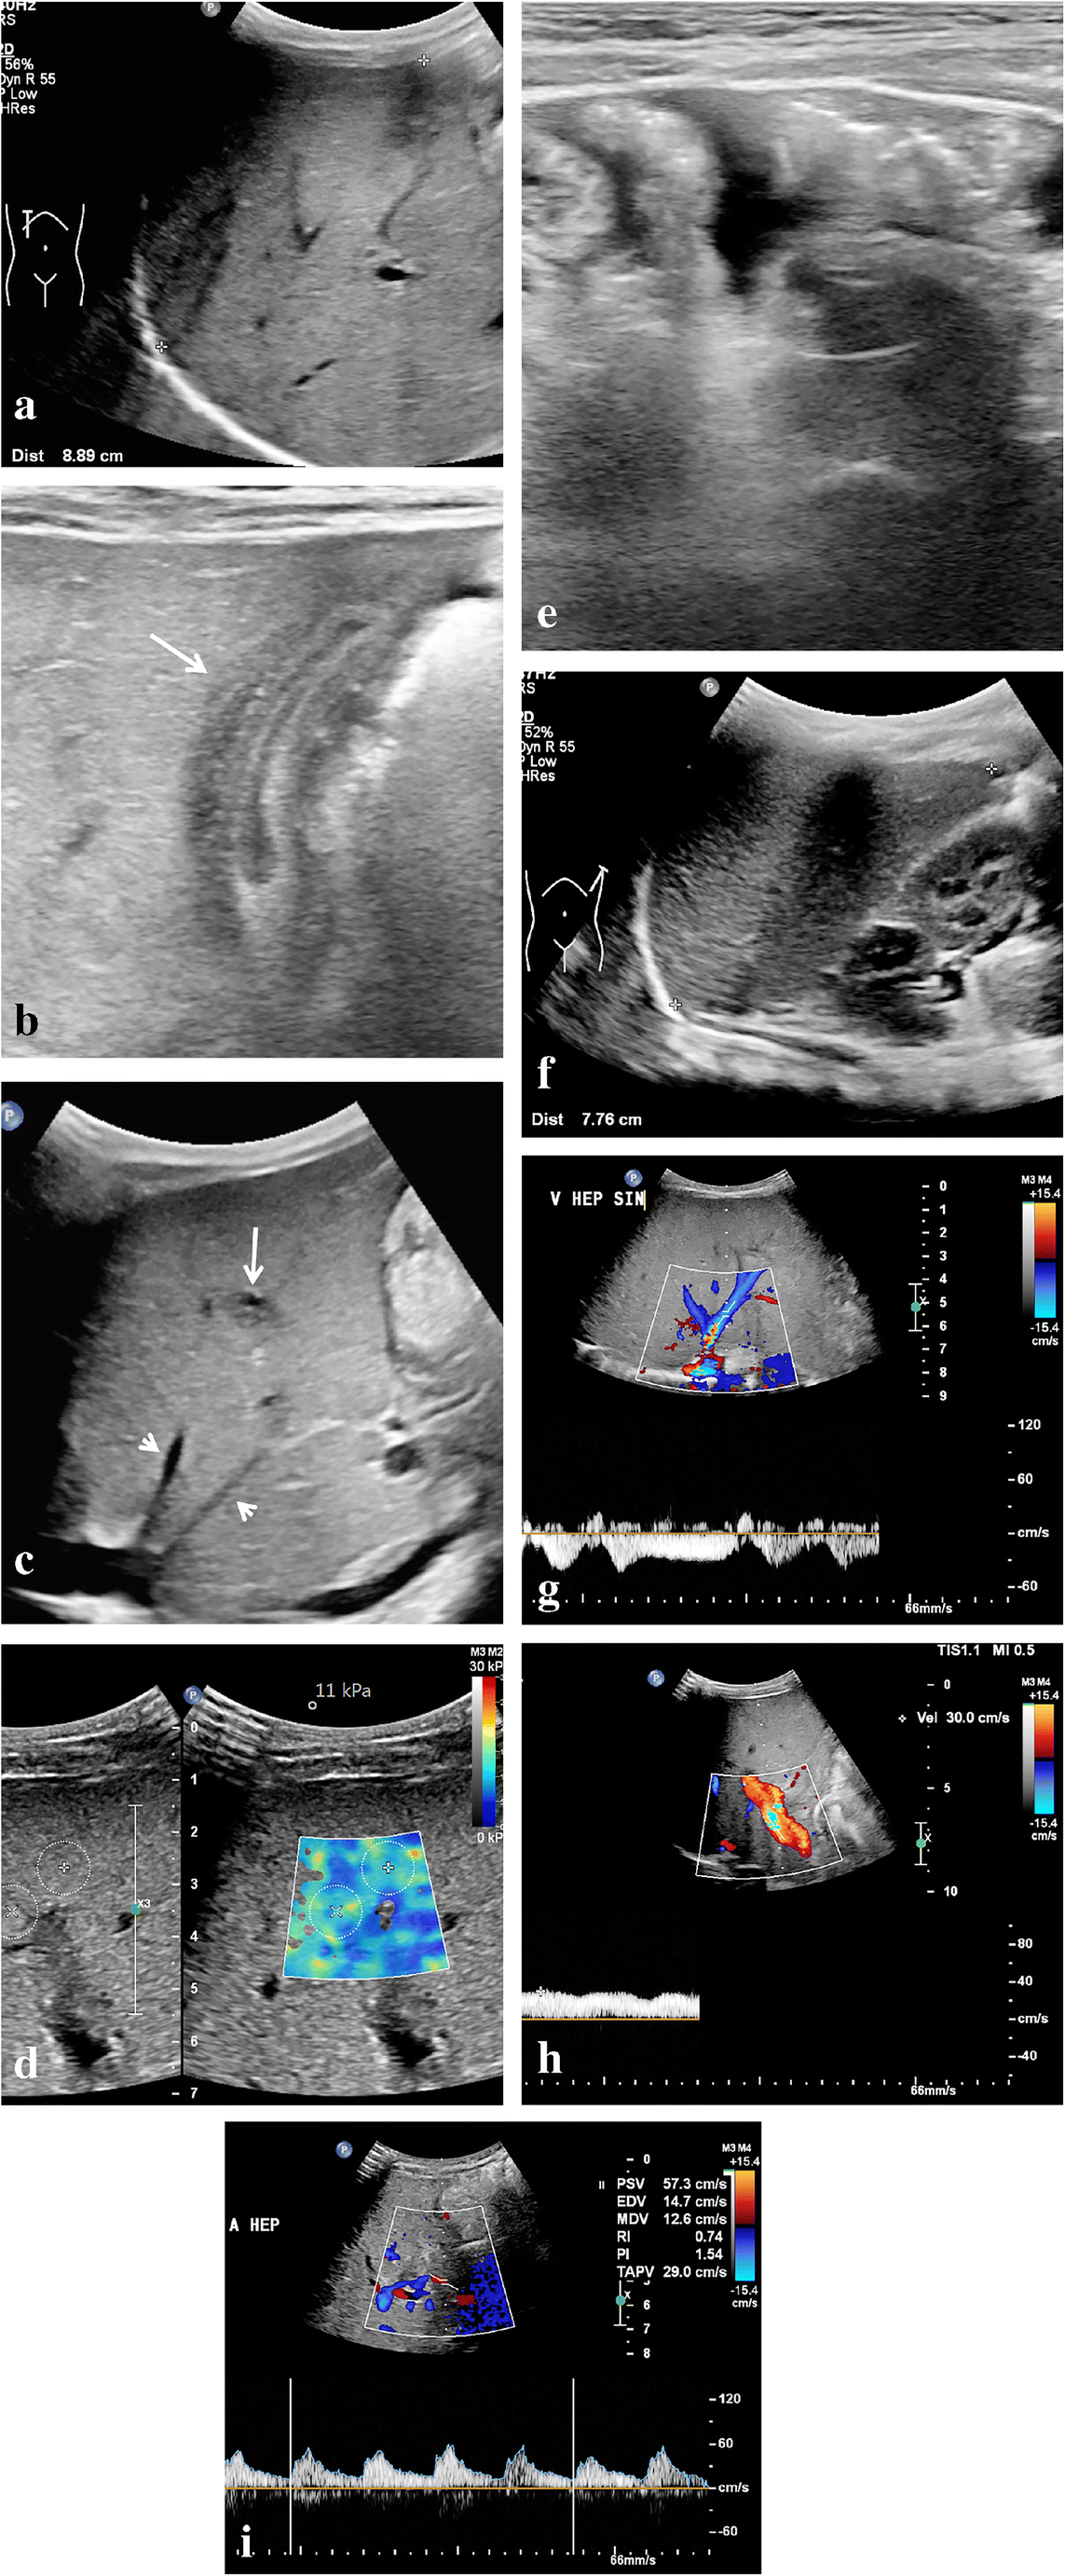

Most of the described US features of sinusoidal obstruction syndrome can be derived from the increased hepatic vascular inflow resistance and hepatic congestion that result from the occlusion of hepatic sinusoids and terminal hepatic venules. Portal vein flow may be increased, normal, or show decreased respiratory velocity variations or increased pulsatility, especially in the early or subclinical stage of sinusoidal obstruction syndrome. Also, segmental (distal) portal vein flow reversal may precede clinical manifestations [25]. Later, flow velocity can decrease, show a to-and-fro pattern or ultimately reverse completely (Fig. 1). The latter two are, however, infrequently observed. Although a specific sign of sinusoidal obstruction syndrome in the appropriate clinical context, portal vein flow reversal occurs generally too late in the disease course to affect early treatment. This is why the recent international expert position statement on sinusoidal obstruction syndrome by Mahadeo et al. [5] stated against using reversed portal flow for diagnosis. Abnormal portal flow characteristics resolve over time with resolution of the clinical sinusoidal obstruction syndrome signs and symptoms. Gallbladder wall edema occurs because of the impaired venous drainage of the gallbladder into the right portal vein. Ascites and gallbladder wall edema were shown to be independent predictors in 70 children with clinically suspected sinusoidal obstruction syndrome after hematopoietic stem cell transplantation [26]. Another example is the absence of the characteristic triphasic hepatic venous outflow pattern as a result of congestion-related loss of liver compliance [14, 17, 19, 27]. Figures 2 and 3 illustrate the spectrum of US findings related to sinusoidal obstruction syndrome in a patient with nephroblastoma and in a patient with neuroblastoma. The latter includes follow-up images and correlation with MRI.

Fig. 1

Different hepatic portal vein flow patterns can be observed in sinusoidal obstruction syndrome. a An axial intercostal transverse color Doppler ultrasound (US) image of the liver shows normal hepatic portal flow direction, velocity and pattern in a 10-month-old boy with juvenile myelomonocytic leukemia who developed severe sinusoidal obstruction syndrome 7 days after allogeneic stem cell transplantation. This was the initial US examination; hepatomegaly and ascites confirmed the clinical suspicion of sinusoidal obstruction syndrome. b An axial intercostal transverse color Doppler US image of the liver in a 4-year old girl with severe sinusoidal obstruction syndrome 21 days after autologous stem cell transplantation, and 5 days after the first clinical suspicion based on elevation of liver transaminases. Increased pulsatility of the portal vein flow pattern with decreased velocities of 10–15 cm/s. c An axial intercostal transverse color Doppler US image of the liver in a 14-year-old girl with neuroblastoma and severe sinusoidal obstruction syndrome shows a to-and-fro flow pattern 5 weeks after autologous stem cell transplantation and 1 week after the first clinical suspicion of the disease. d An axial intercostal transverse color Doppler US image of the liver in a 4-year-old boy with severe sinusoidal obstruction syndrome 29 days after autologous stem cell transplantation shows hepatofugal flow direction in the portal vein. Abnormal portal vein flow patterns resolved on follow-up, in keeping with the clinical resolution of sinusoidal obstruction syndrome

Ultrasound (US) characteristics of mild sinusoidal obstruction syndrome in a 9-month-old boy with right-side nephroblastoma who completed the first month of postoperative treatment with vincristine and actinomycin D. He presented with thrombocytopenia and elevated aspartate transaminase (2-5x above upper limit). A US examination showed several signs complementary to the clinical suspicion of sinusoidal obstruction syndrome. a A sagittal US image shows an enlarged age-related liver size of 8.9 cm. b A transverse high-resolution US image shows gallbladder wall edema (arrow). c A sagittal US image of the liver shows periportal edema (long arrow) and narrowing of the hepatic veins (short arrows). d An axial intercostal elastography measurement of the right liver lobe shows elevated stiffness of 11 kPa (normal stiffness: 5–6 kPa). e A transverse high-resolution US image of the lower abdomen shows mild to moderate ascites. f A sagittal US image of the spleen shows an age-related enlarged spleen of 7.8 cm. g A Doppler US of the liver shows preserved hepatic vein flow pattern. h A Doppler US of the liver shows preserved portal vein flow direction with increased velocity (30 cm/s). i A Doppler US of the liver shows a borderline hepatic artery resistive index of 0.74. Based on the predicted mild to moderate sinusoidal obstruction syndrome, this patient was treated with thrombocyte-transfusion and fluid restriction. The condition of the patient including laboratory values soon improved